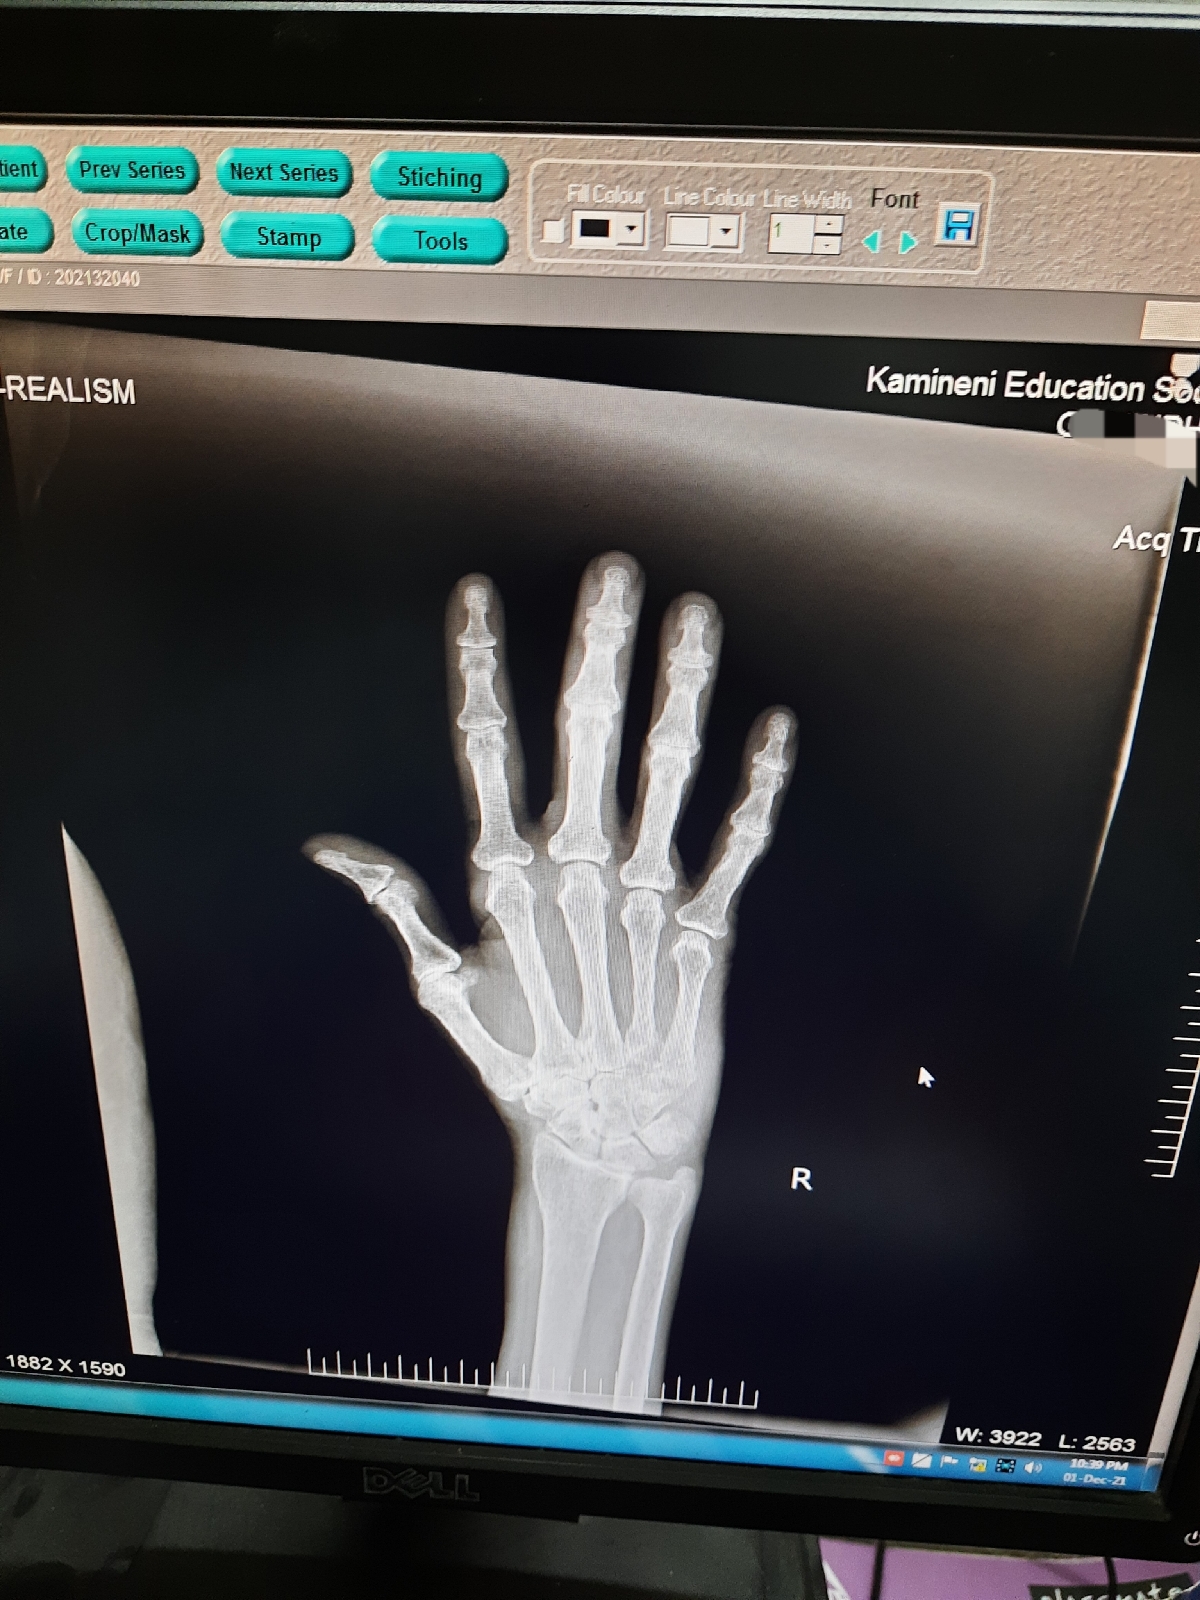

5months back- C/o Rt DIP,PIP,wrist joint pain with restriction of movements

Rt DIP, PIP and wrist - tenderness +, painful ROM+

2. ASSYMETRIC POLYARTHRITIS